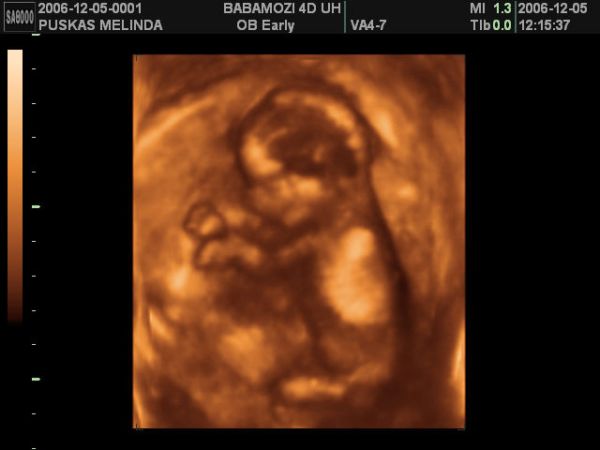

Mi ma voltunk terhesgondozason, megbeszeltuk a szulesi tervunket es nagyon elegedetten tavoztunk, mert abszolut hasonloan gondolkozunk a dokinkkal. Gyakorlatilag senkinek nem kell kompromisszumot kotni senkivel, az alapelveink megegyeznek. Mara meglett a Streptococcus B eredmenyem is, szerencsere ez is negativ, ugyhogy azt mondta, ha folyik a magzatvizem, nincs okom aggodalomra, nem kell rohanni a korhazba, csak mindent szep nyugodtan, ahogy megbeszeltuk. Azt mondta Levi gyakorlatilag kesz, most mar csak rajta mulik, mikor jon, es legyen minden kesz fogadasara. Es hogy ha addig nem, akkor jovo heten talizunk megint. Ettol iszonyu izgatott lettem, olyan jo volt ezt hallani, hogy most mar barmikor nyugodtan johet a baba! En nem tudom mindenki megorul az utolso honapban?!?!?!?